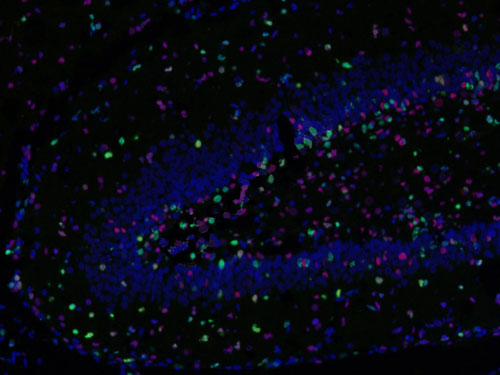

□免疫熒光多標陽性共定位分析:

測量整張掃描切片或者指定區域中單獨通道的數據以及指定共定位的數據(陽性面積或陽性率值表示,選其一)。

免疫熒光空間距離分析:

主要用來研究腫瘤微環境,炎性細胞和腫瘤細胞之間的距離關系等。

□分析一種指標標記的細胞周圍多少微米范圍之內另一指標標記的細胞數量,可以設置不同范圍;

□分析不同指標標記細胞之間的平均距離;

□以某處為界(如腫瘤灶、壞死灶或指定區域等)分析該區域多少微米范圍之內不同指標標記的細胞數量,例如腫瘤周圍500um內CD3陽性細胞的數量。